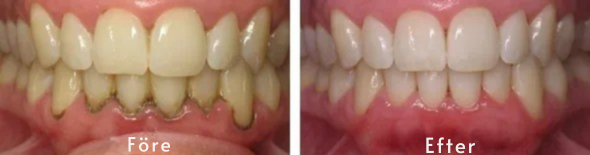

TeethRepair™ Gel har vunnit flera internationella utmärkelser och erkänns av tandläkare som en effektiv behandling som hjälper till att stoppa och återställa tandköttsförlust, stärka tandköttsstödet och skydda exponerade tandrötter, med synliga förbättringar i ditt tandkött efter bara en veckas användning!

Efter den första veckan med TeethRepair™ Gel på dina tillbakadragna tandkött, kommer du att förstå varför våra kunder med tandköttsförlust beskriver det som "livsförändrande."

✅ Känn den omedelbara effekten på tillbakadragna tandkött – Efter bara 5-10 minuter kommer du att känna betydande lindring från känsligheten orsakad av exponerade tandrötter. Efter bara några dagar kommer du att märka att ditt tillbakadragna tandkött börjar läka och fästa sig vid tänderna igen. Med regelbunden användning kommer du att se din tandköttslinje gradvis återvända till en hälsosammare position och skydda dina tänder från farorna med tandköttsförlust.